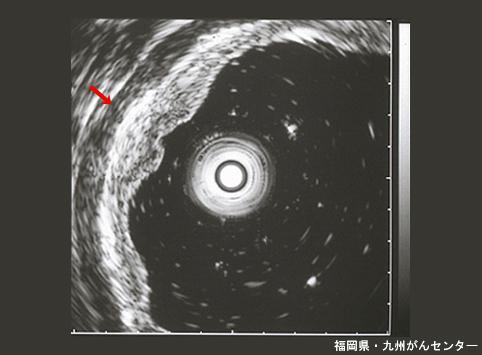

양성 상피성종양 선종 (위)

내시경 점막절제술로 적출된 표면함몰형의 위선종

Fukuoka Pref., 큐슈암센터

양성 상피성종양/선종

위(부위)/전정

초음파

0형(표재형)/IIc형(IIc)

10~14